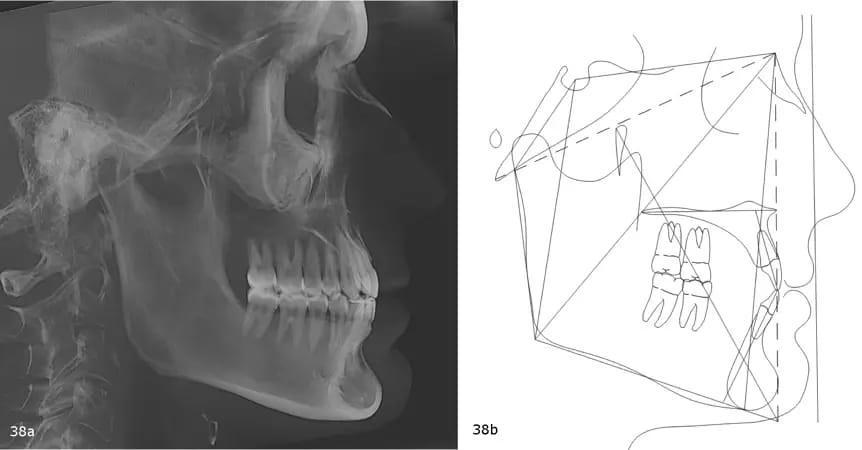

Панорамная рентгенограмма выявила отсутствие третьих моляров, хорошую морфологию корней и параллельность резцов (фото 37). Цефалометрическая рентгенограмма и трассировка показали тенденцию к формированию скелета III класса, характеризующегося коротким основанием черепа и длинной нижней челюстью - чрезмерным развитием нижней трети лица. Наклон верхних резцов внутрь, к нёбу (ретроклинация), и проклинированные (проклонённые) нижние резцы (фото 38).

Фото 38a-b: Дооперационная цефалометрическая рентгенография (a) и трассировка (b).